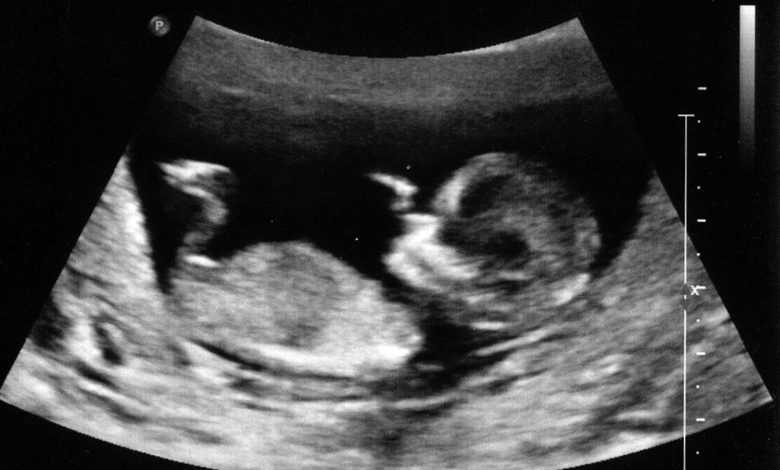

Ұрықтың жүрек соғысы алғаш рет жүктіліктің 5-6 аптасында қалыптасады, бірақ бұл кезде оны қарапайым құлақпен есту мүмкін емес. Ал 7-8 аптадан бастап, УДЗ (ультрадыбыстық зерттеу) көмегімен анық естуге болады. Жүктіліктің 10-12 аптасына қарай жүрек ырғағы тұрақталып, секунд сайын 120-160 соққыға дейін жетеді.

- Ультрадыбыстық зерттеу (УДЗ) – ең алғашқы және кең таралған әдіс.